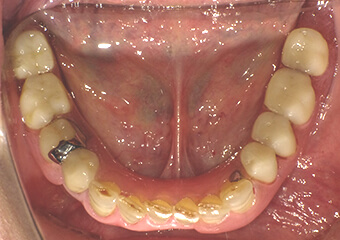

被せ物 施術前

奥歯の金属のかぶせ物、詰め物をセラミックスで再修復しました。セラミックスは欠けやすい(壊れやすい)と言われたのは昔の話で、噛む力にも耐えうる十分な強度を持ち合わせています。周りの色調に合わせるための色付けを省いて作製することで、コストを抑えることもできます。